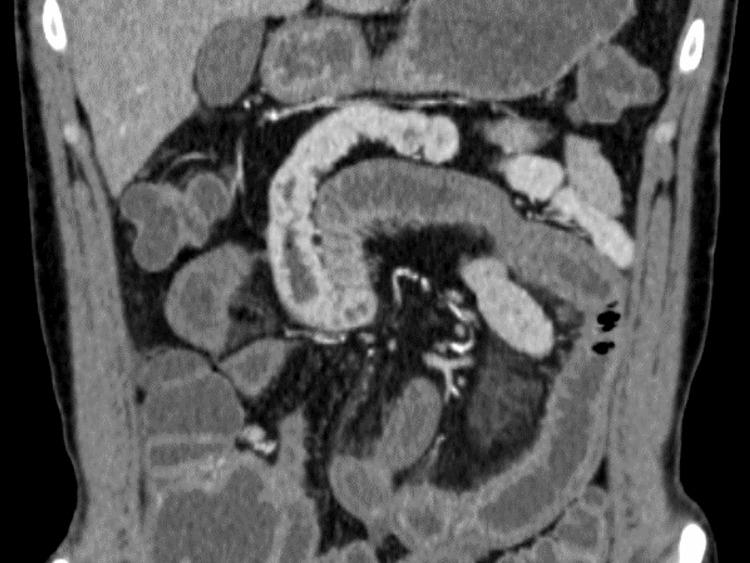

Eosinophilic gastroenteritis (EGE) is a disease involving the gastrointestinal tract that involves the invasion of eosinophils into the lumen of the tract. Invasion of eosinophils in the tract causes edema and inflammation of the wall, resulting in acute or chronic diarrhea and abdominal pain. EGE can cause chronic inflammation in the small intestine, thereby mimicking chronic vasculitis. We report the case of a 24-year-old male patient with the chief complaint of acute progressive abdominal pain. Endoscopic findings of the small intestine were chronic and similar to those of polyangiitis (eosinophilic granulomatosis with polyangiitis). This case shows the presence of various clinical courses of EGE and the discrepancy between the symptoms and endoscopic appearance of vasculitis. Physicians should focus not only on acute symptoms but also on chronic phases of the disease to prevent disease progression and modify patients' help-seeking behaviors according to their symptoms.

摘要

嗜酸性粒细胞性胃肠炎(EGE)是一种累及胃肠道的疾病,其特征为嗜酸性粒细胞侵入胃肠道管腔。嗜酸性粒细胞的侵入会导致肠壁水肿和炎症,进而引发急性或慢性腹泻及腹痛。EGE可导致小肠慢性炎症,从而类似慢性血管炎。我们报告一例以急性进行性腹痛为主诉的24岁男性患者。小肠内镜检查结果为慢性,与多血管炎(嗜酸性肉芽肿性多血管炎)相似。该病例显示了EGE存在多种临床病程,以及血管炎症状与内镜表现之间的差异。医生不仅应关注急性症状,还应关注疾病的慢性阶段,以防止疾病进展,并根据患者症状调整其就医行为。